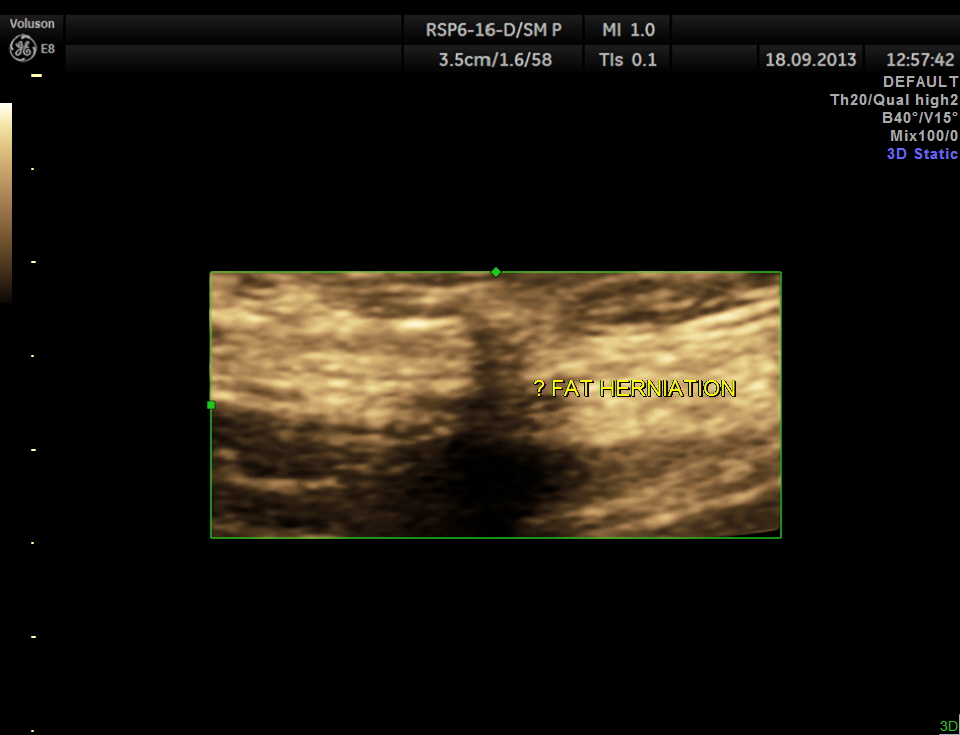

Scan with high resolution probe over the point of maximal tenderness revealed peritoneal fat herniation.

the next image is a 3 D reconstruction.